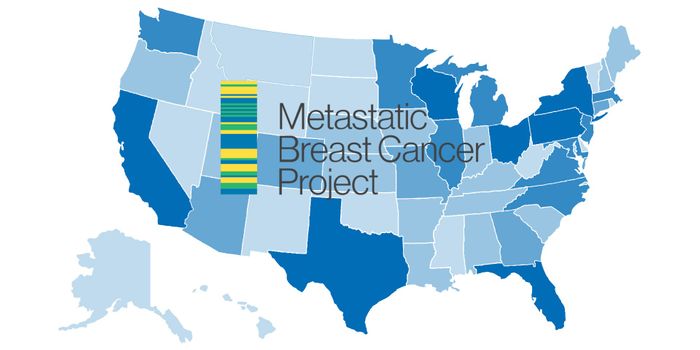

OCT 18, 2017VideosIn 2016, an estimated 246,660 women in the US was diagnosed with breast cancer - a disease that currently ranks as one o ...